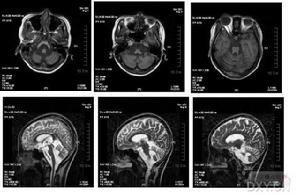

遺傳性共濟失調2、Friedreich型共濟失調(FRDA)X片可見脊柱和骨骼畸形;MRI可見脊髓變細;心電圖常見T波倒置、心律失常和傳導阻滯,超聲心動圖示心室肥大,視覺誘發電位波幅下降。